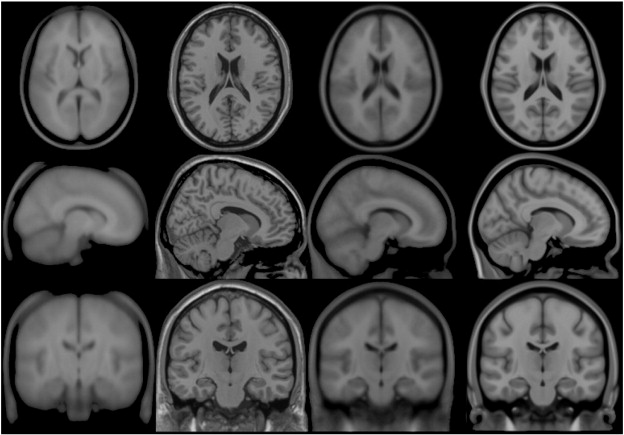

Colin27

In 1998, a new atlas with much higher definition than MNI305s was created at the MNI. One individual (CJH) was scanned 27 times and the images linearly registered to create an average with high SNR and structure definition (Holmes et al., 1998). This average was linearly registered to the average 305. This dataset was originally intended for an ROI parcellation scheme to be used with ANIMAL non-linear spatial normalization (Collins et al., 1995).

Transverse, sagittal and coronal views of four generations (all T1-weighted images) of MNI space template from left to right. Note that MNI52 has greater z-axis coverage than MNI305 and that the 40th-generation non-linear MNI152 combines the detail apparent in the single subject Colin27 template with the group representativeness of MNI305 or MNI152.